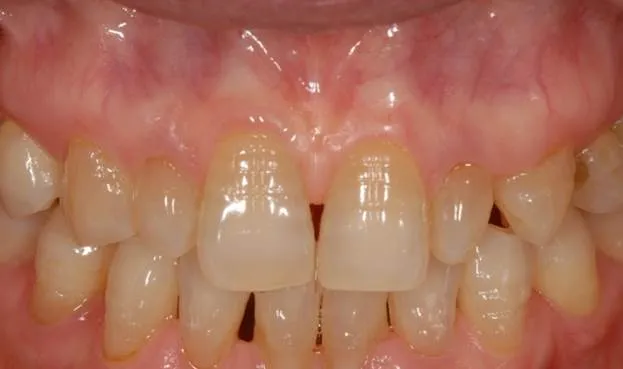

治療後

治療その後

術後4ヶ月